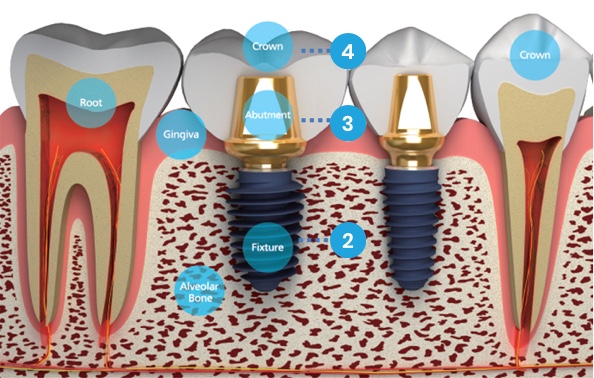

A dental implant is a small titanium screw that is placed in the jaw to act as a fixed and permanent root. During the healing process this screw integrates with the surrounding bone (through a process known as osseointegration) to create a strong and lasting foundation that can then be used to support a dental crown, multiple bridge, or fixed denture.

What is an implant?

Abutment placement

The abutment is the connecting element between the crown and the implant.

The abutment is connected to the implant during or after the healing period, depending on the stability of the implant that gradually integrates with the surrounding bone to create a strong and lasting foundation.